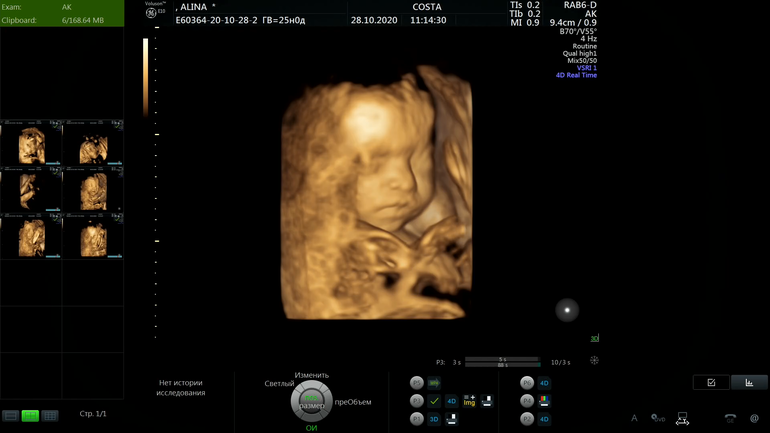

На сроке 25.1 были мы с малышкой на узи😊 ровно в срок развивается, вес был 808 гр, такая большая уже моя девочка 😍

Наше фото, вот такая серьезная девочка у меня там в животике 😁 По мне она копия моего сына 😀 значит копия мужа 😁